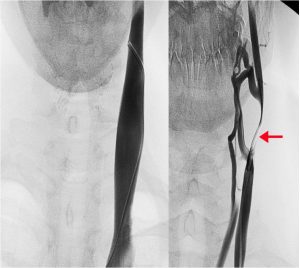

Chronic cerebrospinal venous insufficiency (CCSVI) is a newly described vascular entity. It is characterized by restricted venous outflow from the brain and spinal cord through the internal jugular (IJV) and/or azygos (AZ) veins (Figure 1), or sometimes, through the external vertebral plexuses. (1-5) Clinical Vignette: CCSVI in multiple sclerosis patients A 41 year old woman,…